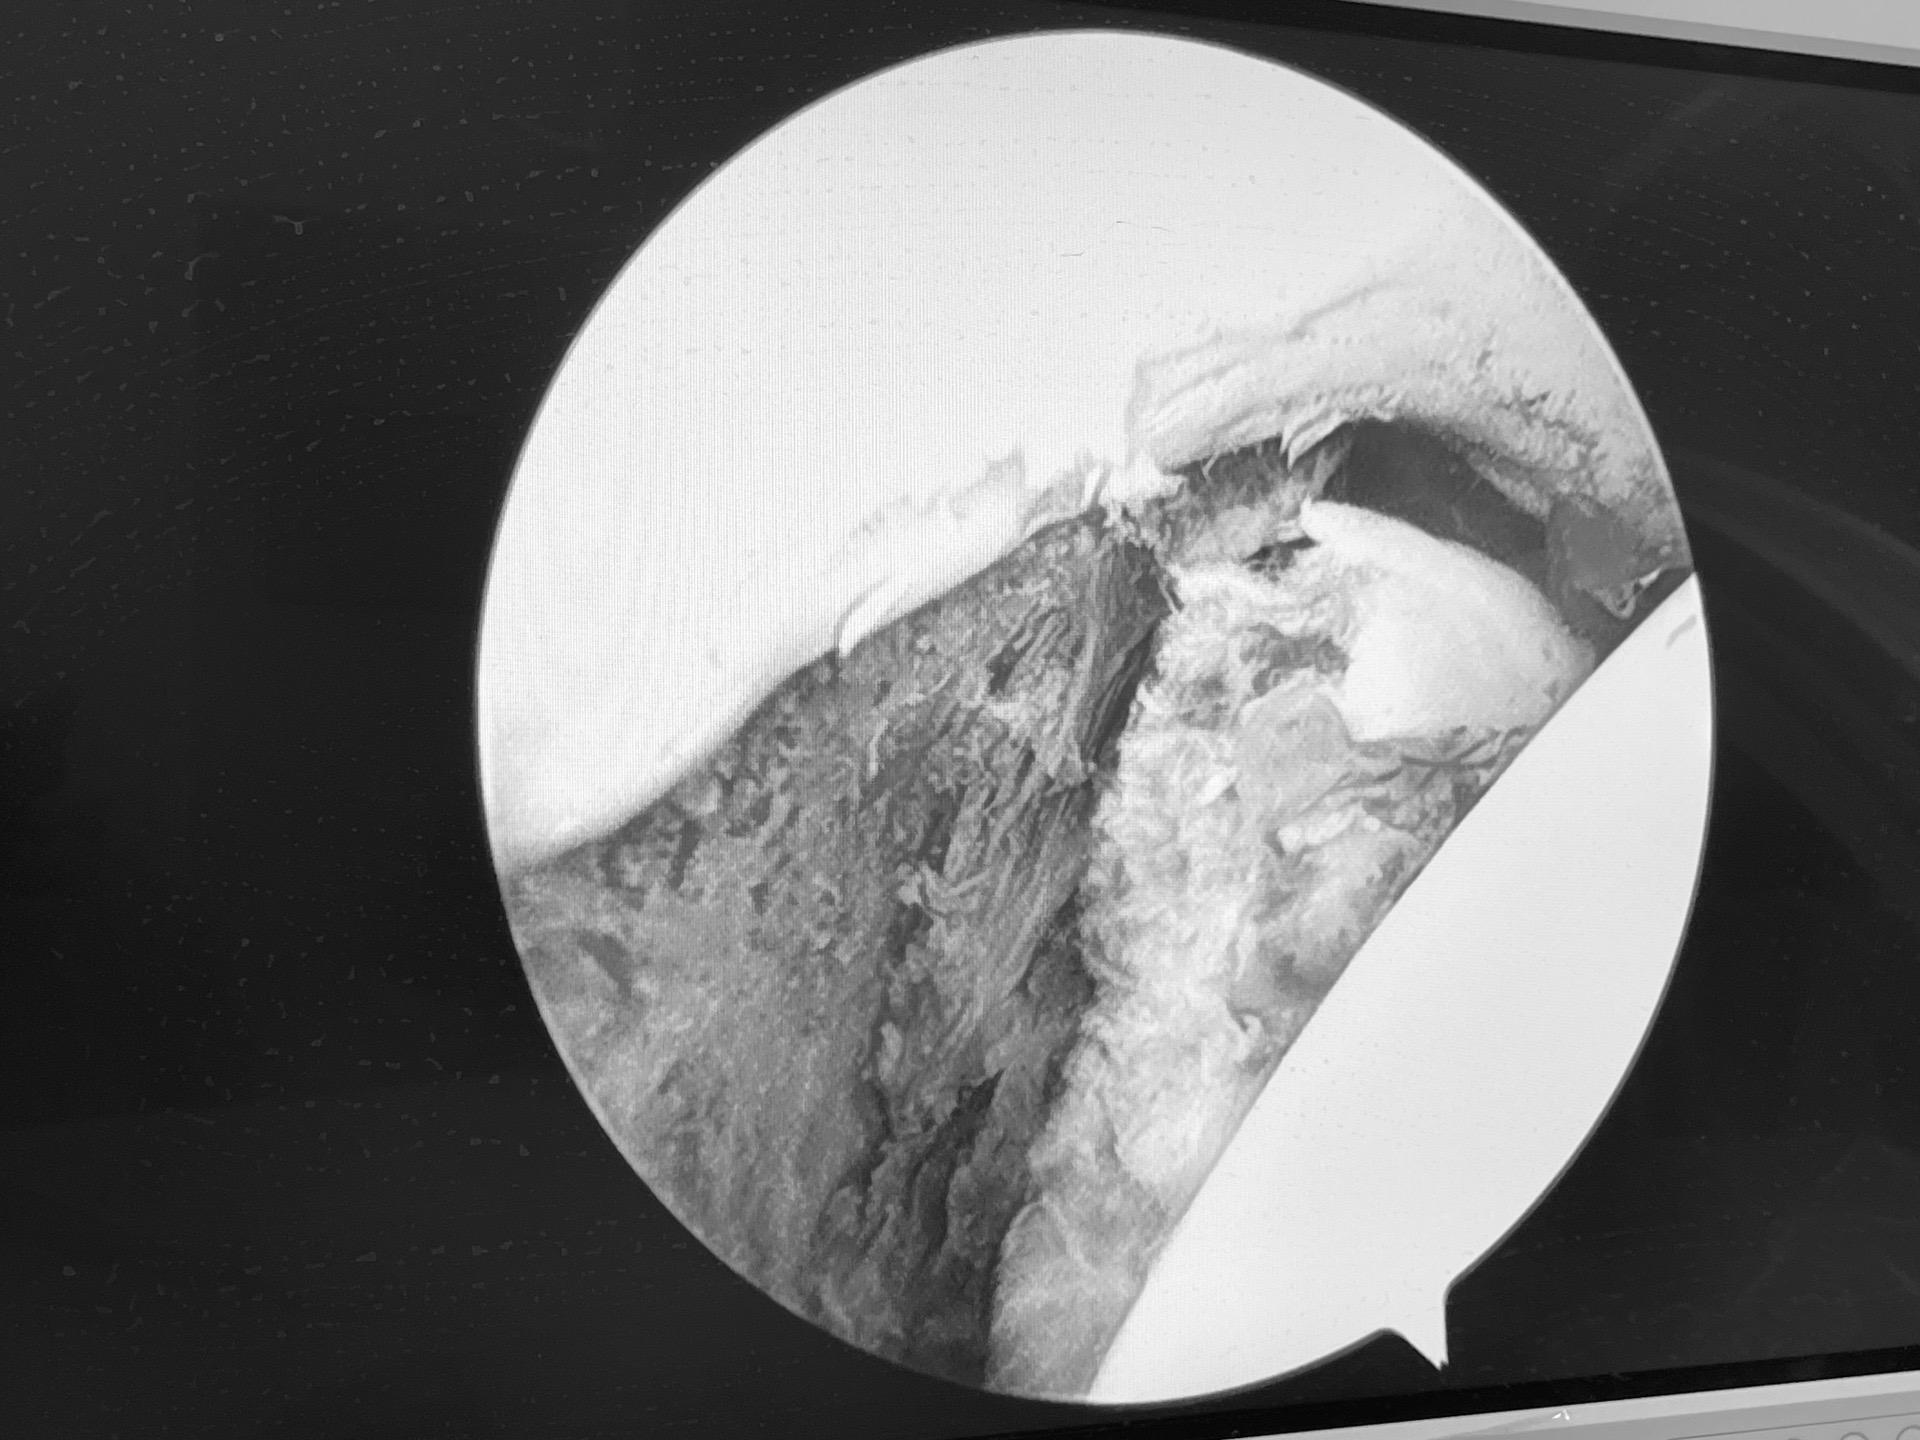

髋关节镜下游离体取出。髋关节脱位,股骨头圆韧带撕脱性骨折,髋关节镜下取出游离骨块。